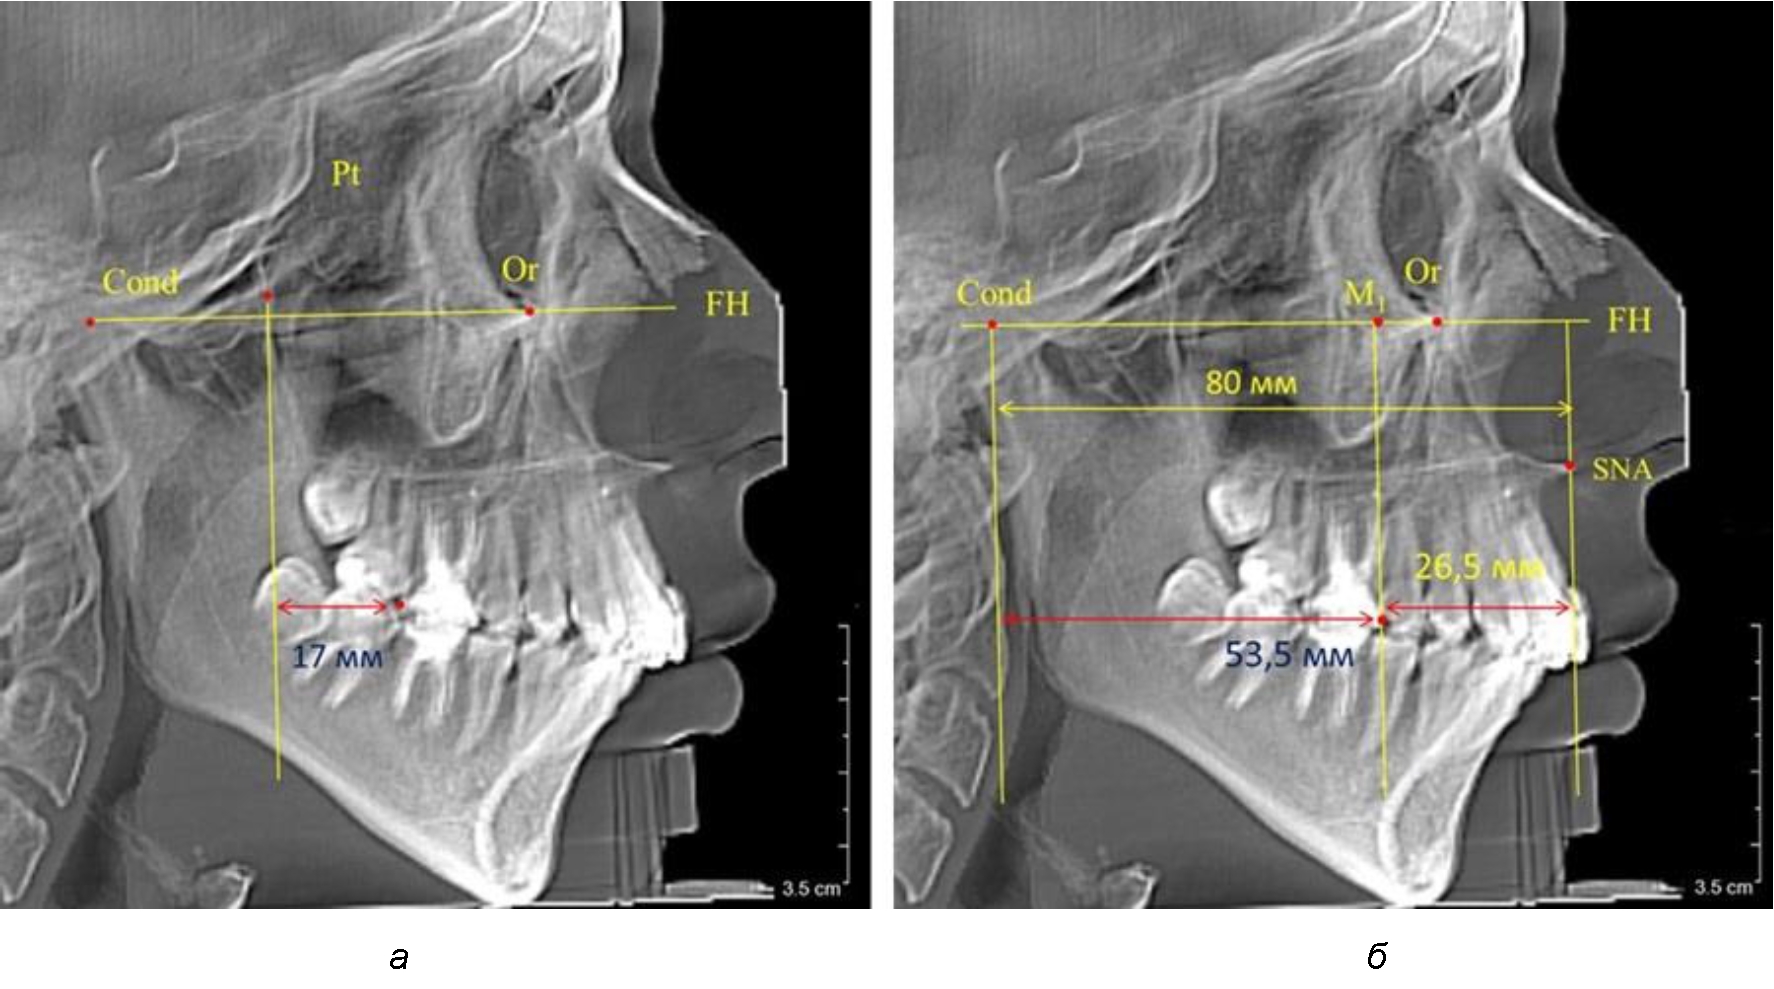

Рис. 2. Особенности положения первых моляров по R. E. McDonald (а) и по предложенному методу (б) при уменьшенном молярно-крыловидном расстоянии

Так, при расстоянии от крыловидной вертикальной плоскости PTV до дистальной поверхности верхнего первого постоянного моляра в 13 мм сагиттальный размер гнатического отдела был 82 мм. При этом отношение кондилярно-спинального расстояния к кондилярно-молярному размеру (54,5) было близким к коэффициенту 1,5, что представлено на рис. 2.